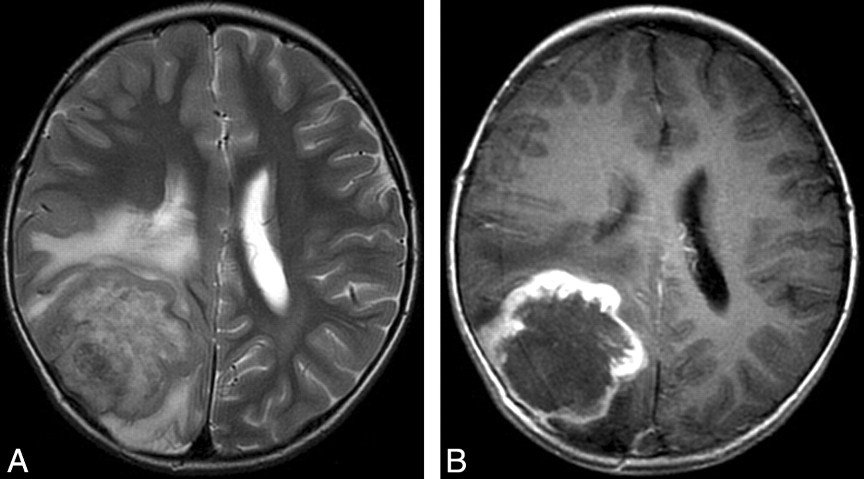

Гемангиоперицитома диагностируется с помощью таких методов исследования, как УЗИ, КТ, МРТ и ангиография. Подтвердить диагноз помогают пункционная биопсия и гистологический анализ взятого участка патологической ткани.

Диагностика гемангиоперицитомы включает в себя комплексное обследование, которое может включать физикальный осмотр, визуализирующие исследования (такие как МРТ или КТ), а также биопсию для гистологического анализа. Важно также провести дифференциальную диагностику с другими типами опухолей.